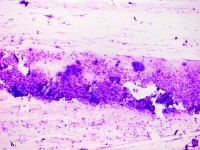

De Tzanck reuscellen hebben in het Diff-Quick preparaat een lichtblauw (basofiel)

cytoplasma en een homogene donkerblauwe of paarse kern (hyperchromatisch, sterk

aankleurend), en zijn zeer groot, veel groter dan een granulocyt. Het zijn geen

macrofagen of Langhanse reuscellen, het zijn conglomeraten van grote epitheliale

cellen (keratinocyten). Er kunnen in het preparaat ook losse van deze grote

hyperchromatische epitheelcellen liggen, maar diagnostisch is het vinden van

een klompje waarbij het cytoplasma samengesmolten is en de kernen tegen elkaar

aanliggen. Losliggende grote afgeronde epitheelcellen (Tzanck cells) kunnen

![Tzanck test met multinucleate giant cells (click on photo to enlarge) [source: www.huidziekten.nl] Tzanck test met multinucleate giant cells](../../../images/soa/Tzanck-test-5z.jpg) |

Tzanck

test |